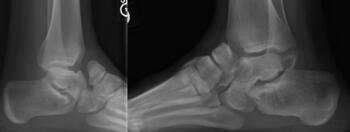

Here is a typical case presentation. A 21-year-old Marine at Ft. Leonard Wood for training underwent a Cincinnati release at one year old and had stellar follow-up. Her surgeon even wrote her medical waiver for entrance into the Marines. She ran track in high school. She finished boot camp and completed all of her Marine training, but now has chronic pain. She no longer can run. She hasn’t passed her physical training in over a year. She developed talonavicular DJD. By all accounts, her overall clubfoot should be rated an A+; no residual deformity, normal talocalcaneal angles on AP and lateral views, no equinus, no residual varus, only slight met primus elevatus, but no signs of a flattop talus. Clinically, she lacks subtalar range of motion, which I commonly find post-clubfoot release of any kind. So many in the military do very well for a while, but the demands of the military eventually catch up to them. We all root for clubfeet to make it, but the odds are stacked against them.